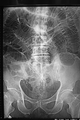

File:SBO plain.png

Abdominal Drain Causing Early Small Bowel Obstruction After Laparoscopic Colectomy Poon CM, Leong HT - (2009 Oct-Dec)

| actual | 19:09 4 may 2015 | 512 × 767 (379 kB) | Rossdonaldson1 (discusión | contribs.) | OPENi Abdominal Drain Causing Early Small Bowel Obstruction After Laparoscopic Colectomy Poon CM, Leong HT - (2009 Oct-Dec) |